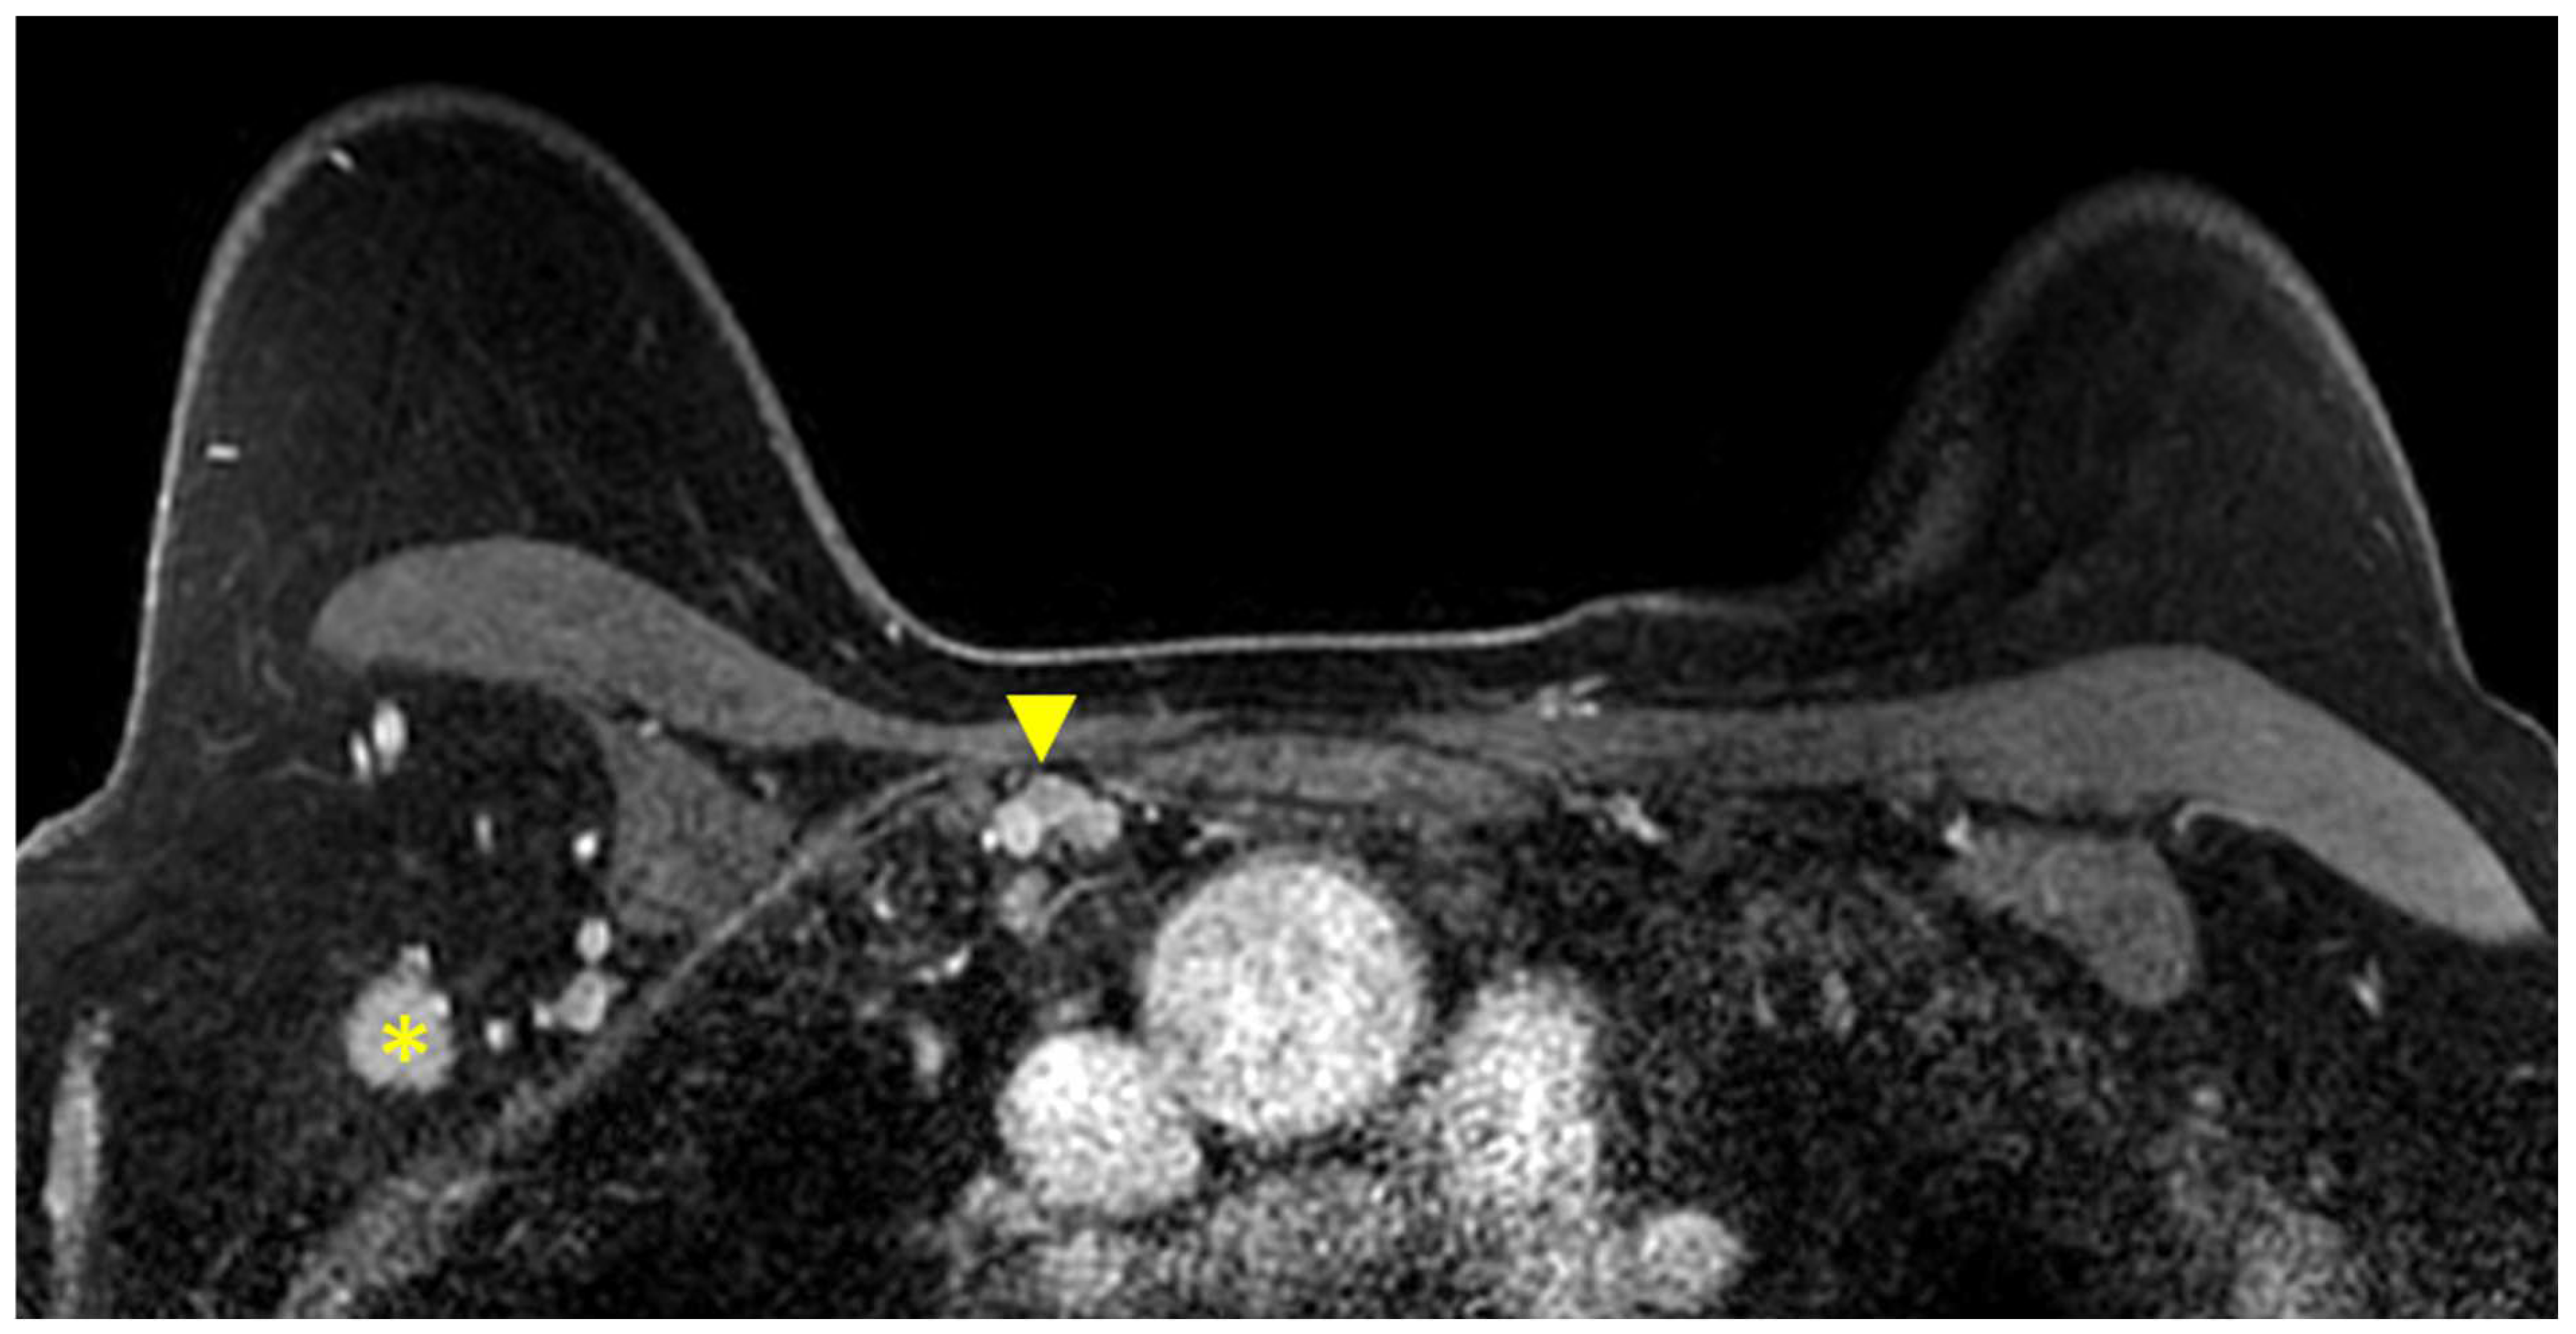

Figure 5.

Anatomy of the axillary nodal stations on axial T1W fat-suppressed post-contrast breast MRI. Levels are defined by the relationship of the lymph node to the pectoralis minor muscle (asterisk).

Figure 6.

Axial T1W fat-suppressed post-contrast breast MRI provides a global view of the axillary and internal mammary nodal basins. In this case, level I axillary adenopathy (asterisk) and internal mammary adenopathy (arrowhead) are present.